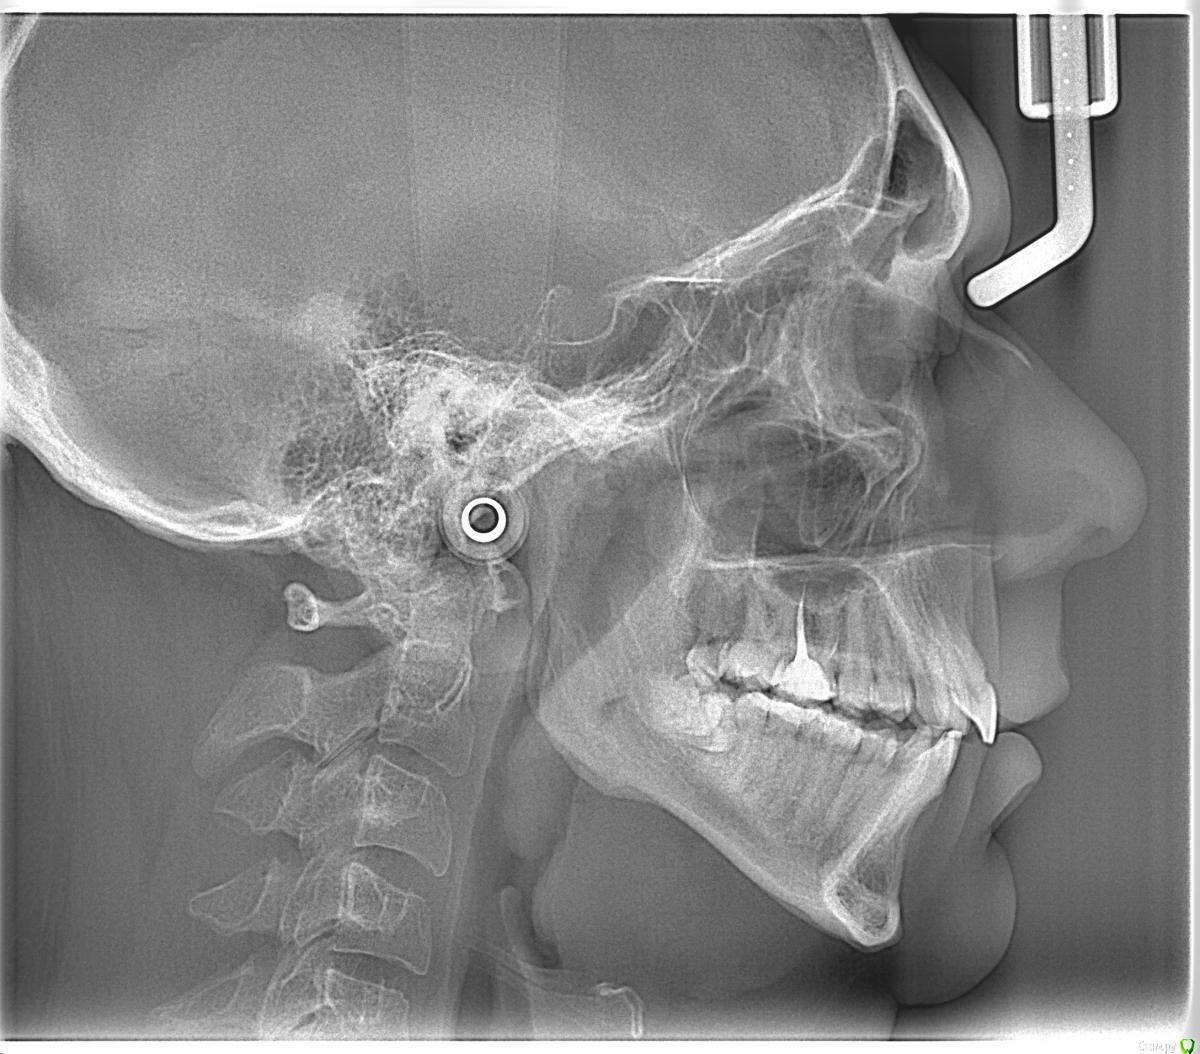

Здравствуйте, Коллеги. Вот такой вот случай, пациент 32 года. Изначально, хотел дистализировать в первом сегменте с целью апрайтинга 13 - 16, провести апрайтинг боковых зубов н/ч, затем САРПЕ и MEAW, понятно, что восьмерки долой еще до лечения. Но потом увидел форму корней 37, 47 (это не искажение, по КТ они и правда такие) и кисты прорезывания за ними. В связи с этим мне кажется, что апрайтинг снизу невозможен, так как эти верхушки никуда меня не пустят, разве что ввиду проблем с пародонтом семерки тоже уйдут. Вопрос: что делать??? Даже если отбросить мультилуп и готовить его на ортогнатию, то апрайт все-равно нужен, как поступить? Заранее спасибо!

P.S.: Забыл... сверху семерки такие же.